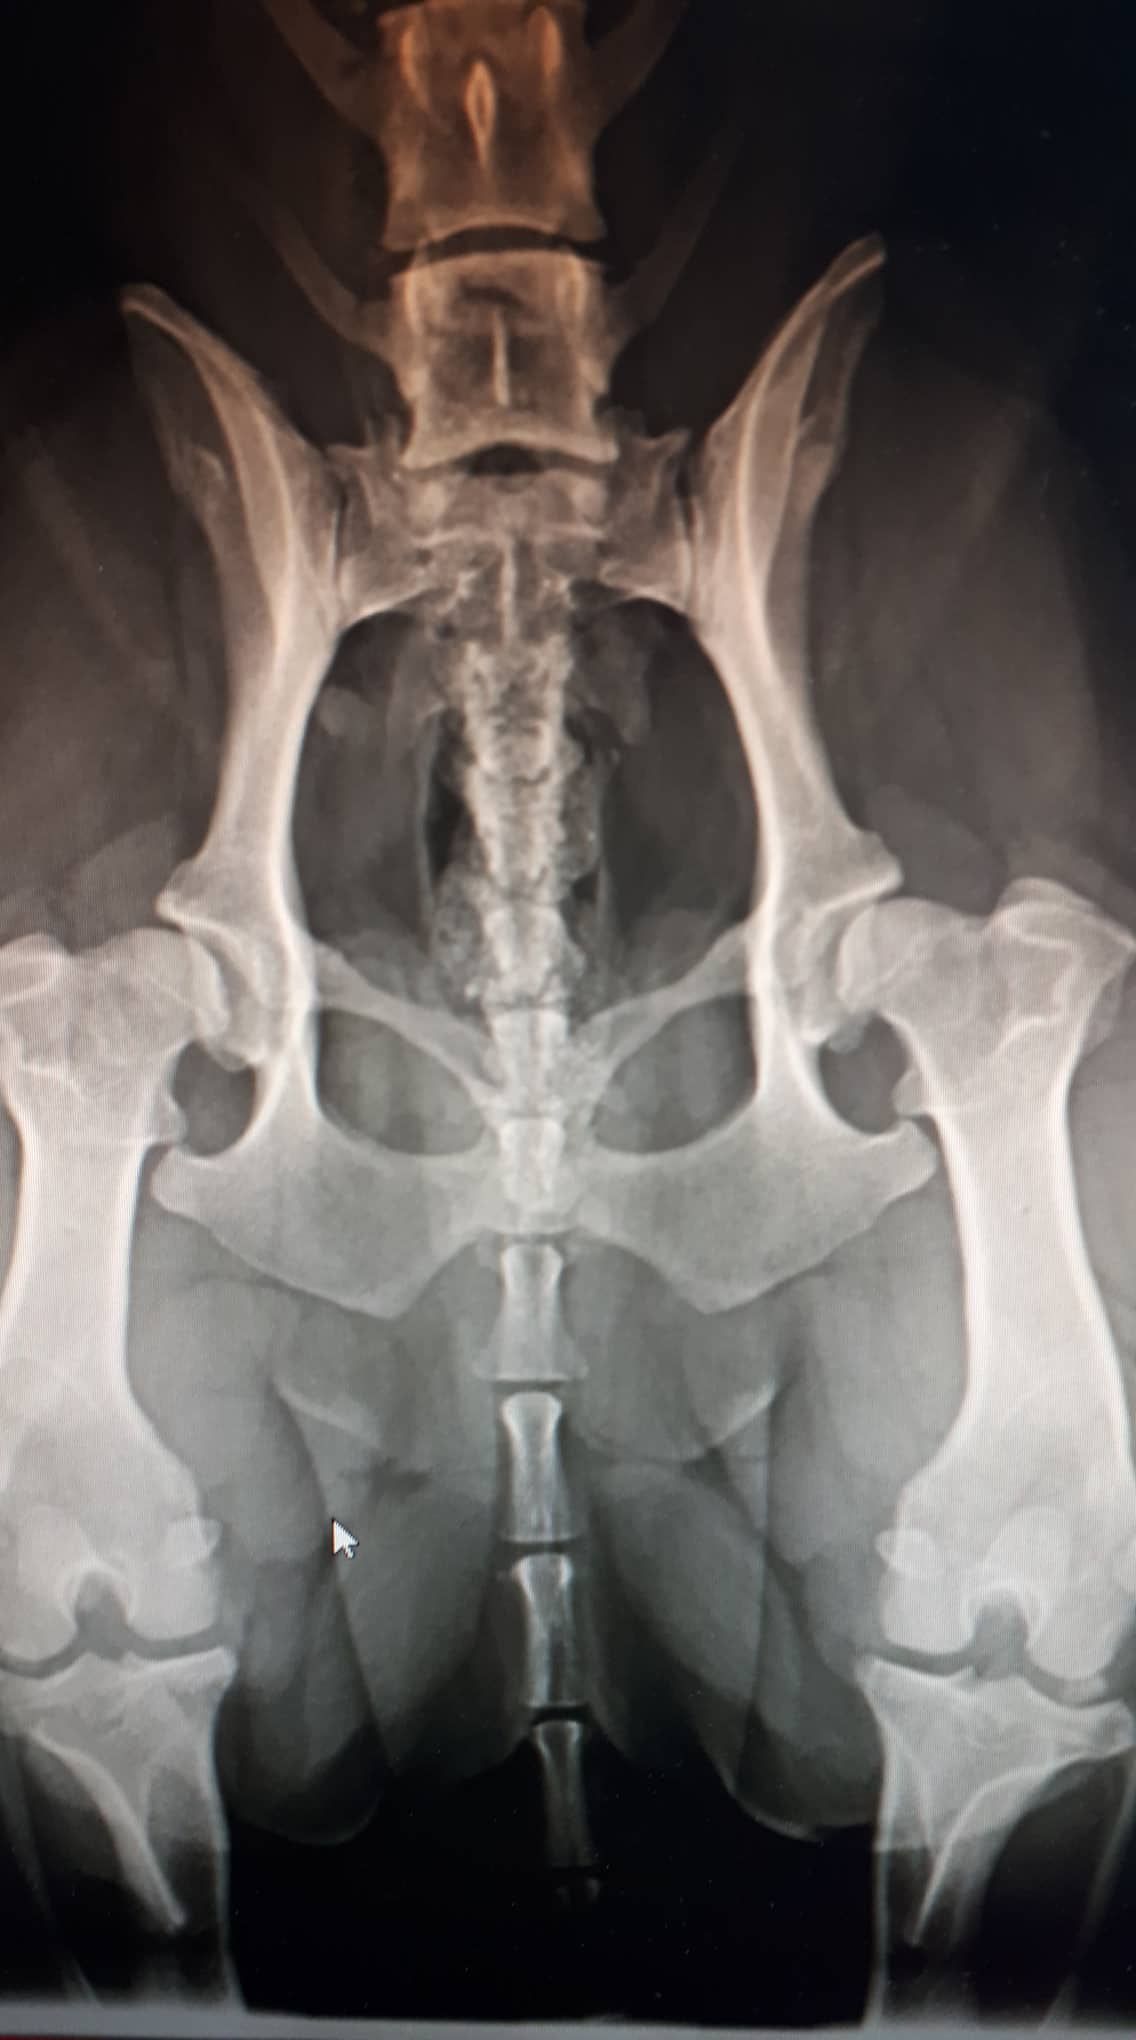

This document presents a detailed analysis of corgi hip x-rays, offering a systematic examination of the radiographic data collected from various subjects. The study is focused on the utilization of x-ray imaging to assess the anatomical structure and integrity of the hip joints in corgis, which is critical for the early identification and quantification of dysplastic changes.

The images have been evaluated using established radiographic protocols and standardized scoring systems, including the Orthopedic Foundation for Animals (OFA) criteria. These metrics provide a quantitative basis for assessing hip conformation and diagnosing potential anomalies. Through this analysis, the data aims to contribute to a more objective understanding of hip joint health and to support future research in veterinary orthopedics.

In the following sections, a curated list of hip x-rays is presented alongside pertinent observations and discussion of the imaging findings (added at a later point).

Excellent